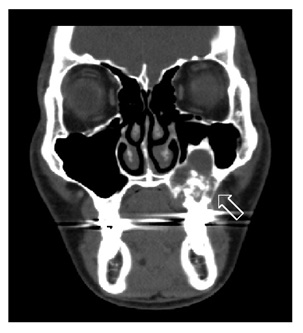

Maxillary Ameloblastoma: A Pictorial Case Report

Chu YK